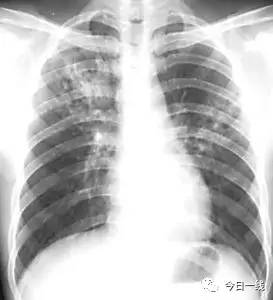

(肺结核 网络图)